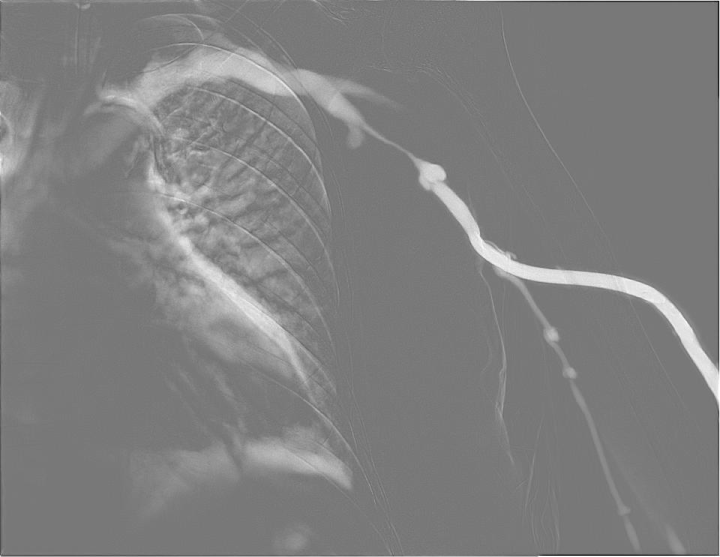

투석중 혈류 저하,

풍선확장술로 회복

시술 전

시술 후